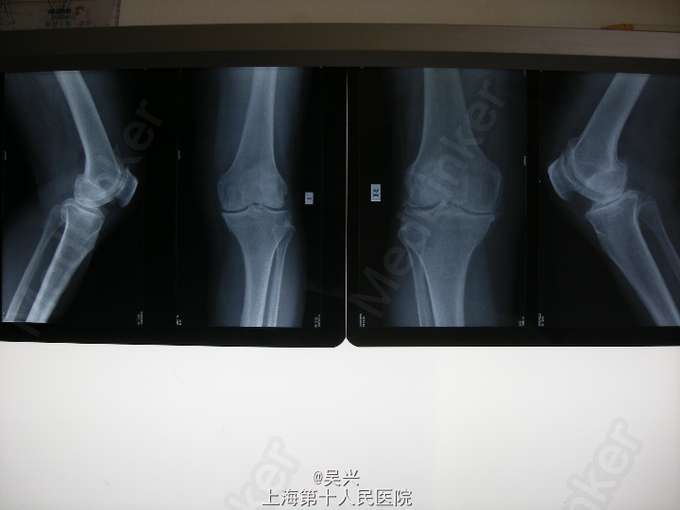

双膝关节置换术

患者,女,65岁。双膝肿痛、活动受限5年,保守治疗无效。

查体:双膝肿胀、压痛,内翻畸形,中度屈曲挛缩。 辅查:X线片示双膝严重骨关节炎。

诊断:双膝严重骨关节炎 处理:完善术前准备后,行双侧同时膝关节表面置换术。